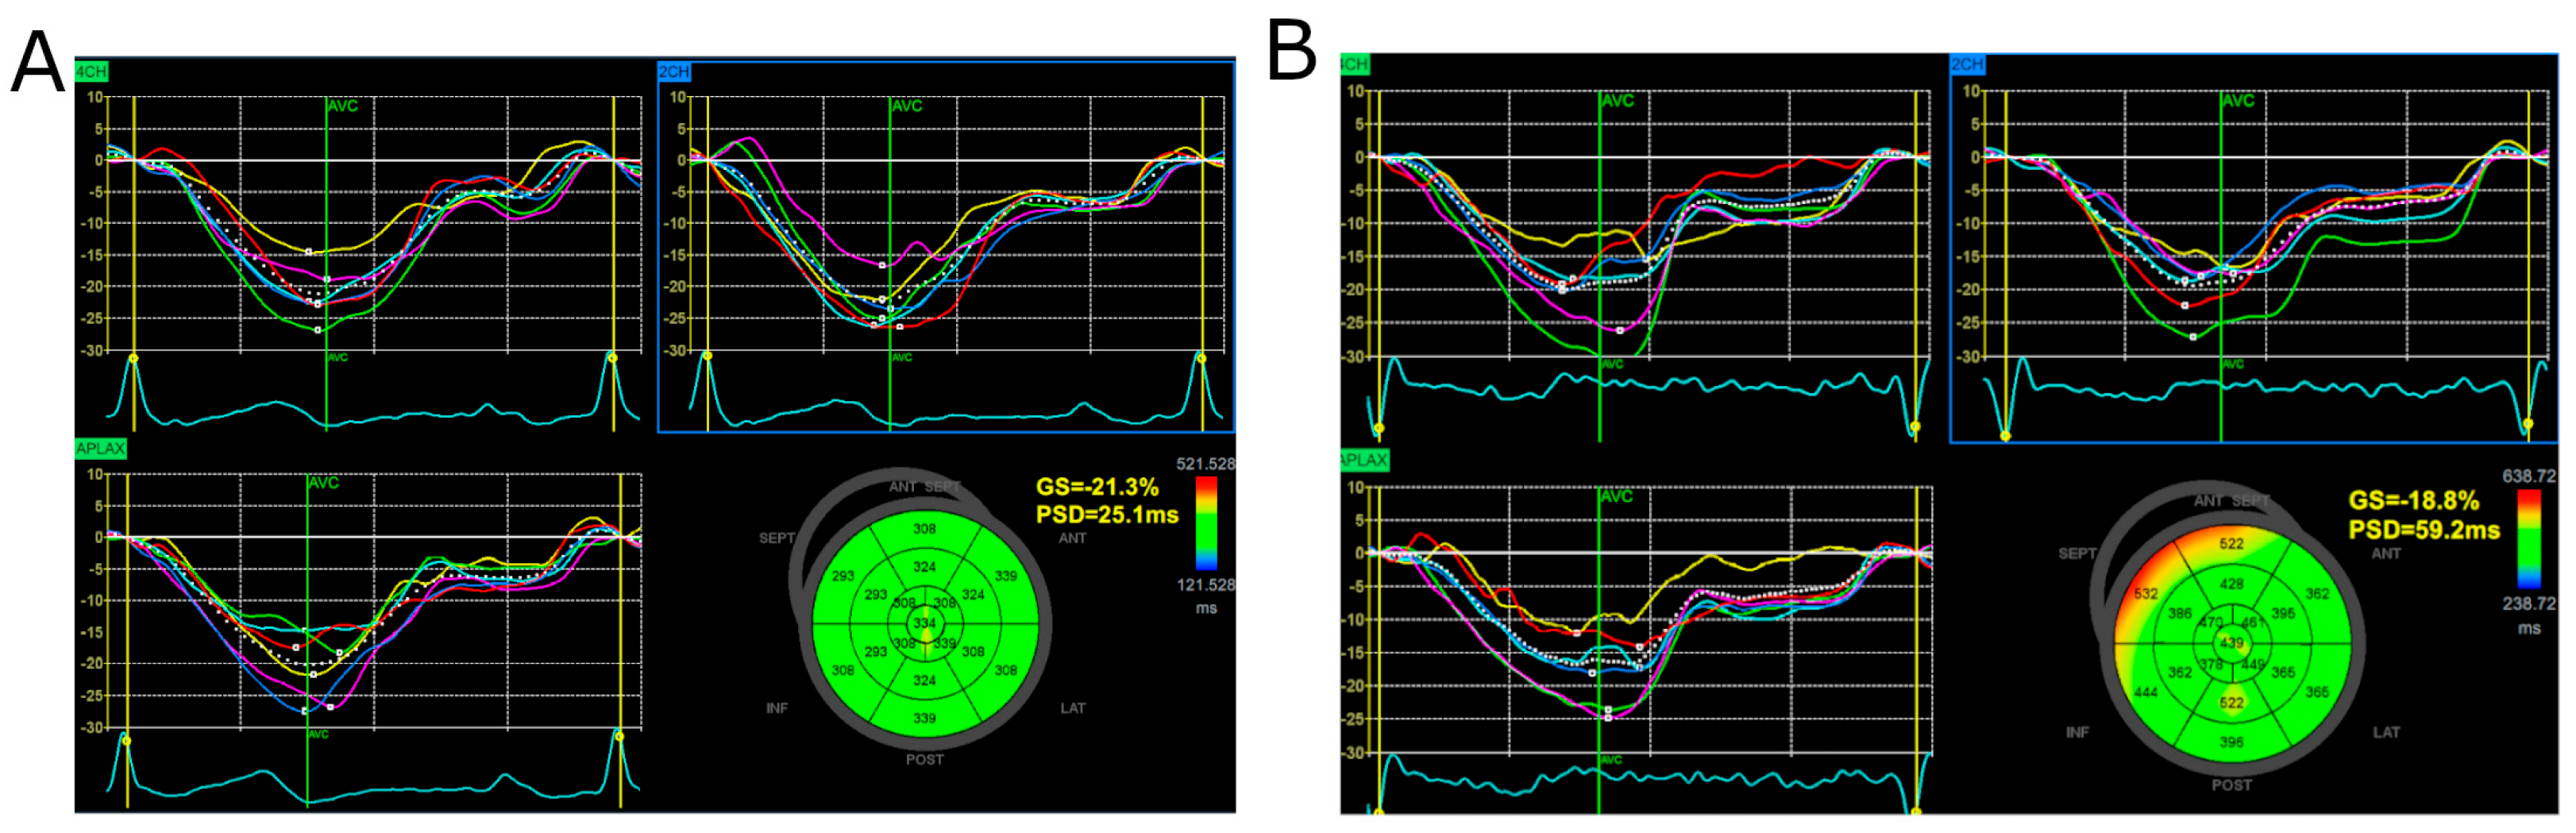

3.2. Global Longitudinal Strain, Peak Systolic Dispersion, and Myocardial Work Indices

4. Discussion

4.1. Summary of Findings

4.4. PSD as an Indicator of Left Ventricular Contraction Inhomogeneity